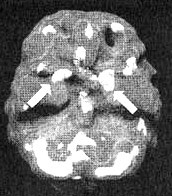

Мозг Марты — паническое расстройство

Иллюстрация к книге — Измените свой мозг - изменится и жизнь! [i_039.jpg]

Трехмерное изображение — активный мозг, вид снизу. Обратите внимание на повышенную активность базальных ганглиев справа (помечено стрелкой).